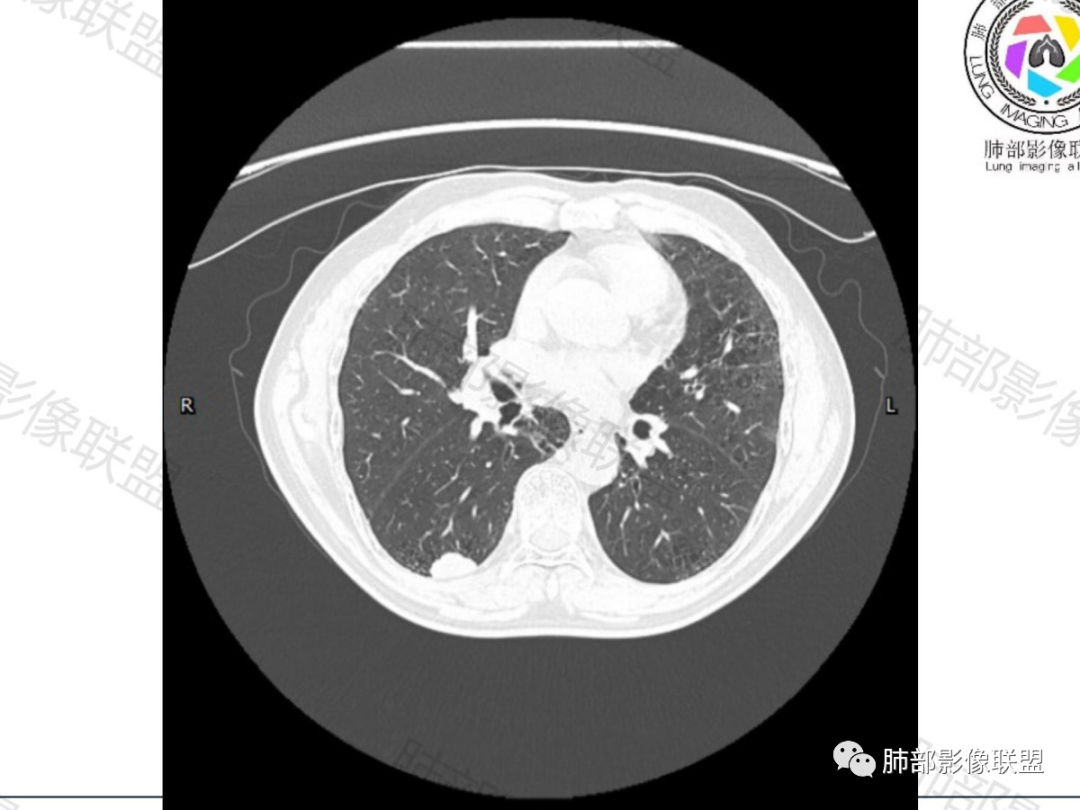

老年男性,有肺气肿背景(提示可能吸烟)

右肺下叶实性结节,有山丘征,右肺门可见淋巴结

首先考虑小细胞癌

晨读:男,66岁,发現肺部结节1月。胸部CT:间隔旁肺气肿背景,右肺下叶实性结节,居于气肿与正常肺交界处。治疗前边缘有渗出,内基底段也有渗出灶,治疗后结节边界清晰,内基底段渗出消失。结节广基与胸膜相接,山丘,边缘膨隆、棘突、指状突起,空泡,血管集束,似有支气管在边缘截断,平扫密度尚均匀,增强后轻度不均匀强化。考虑Ca,小C?大C?鉴别PC等。

右肺下叶实性结节,肺气肿背景

抗炎治疗后周围渗出减少,结节大小无明显变化

形态呈山丘样改变,边缘膨隆

指状突起

浅分叶

胸膜下脂肪间隙不清

增强后不均匀强化,中心可见边界不清低密度坏死区,沼泽样坏死

右肺下叶实性结节,肺气肿背景,山丘,边缘膨隆、指状突起。治疗前边缘有渗出,治疗后结节边界清晰,大小变化不大。胸膜下脂肪间隙不清,增强后轻度不均匀强化,内部沼泽样坏死。

恶性问题不大,倾向小细胞肺癌。

小细胞肺癌